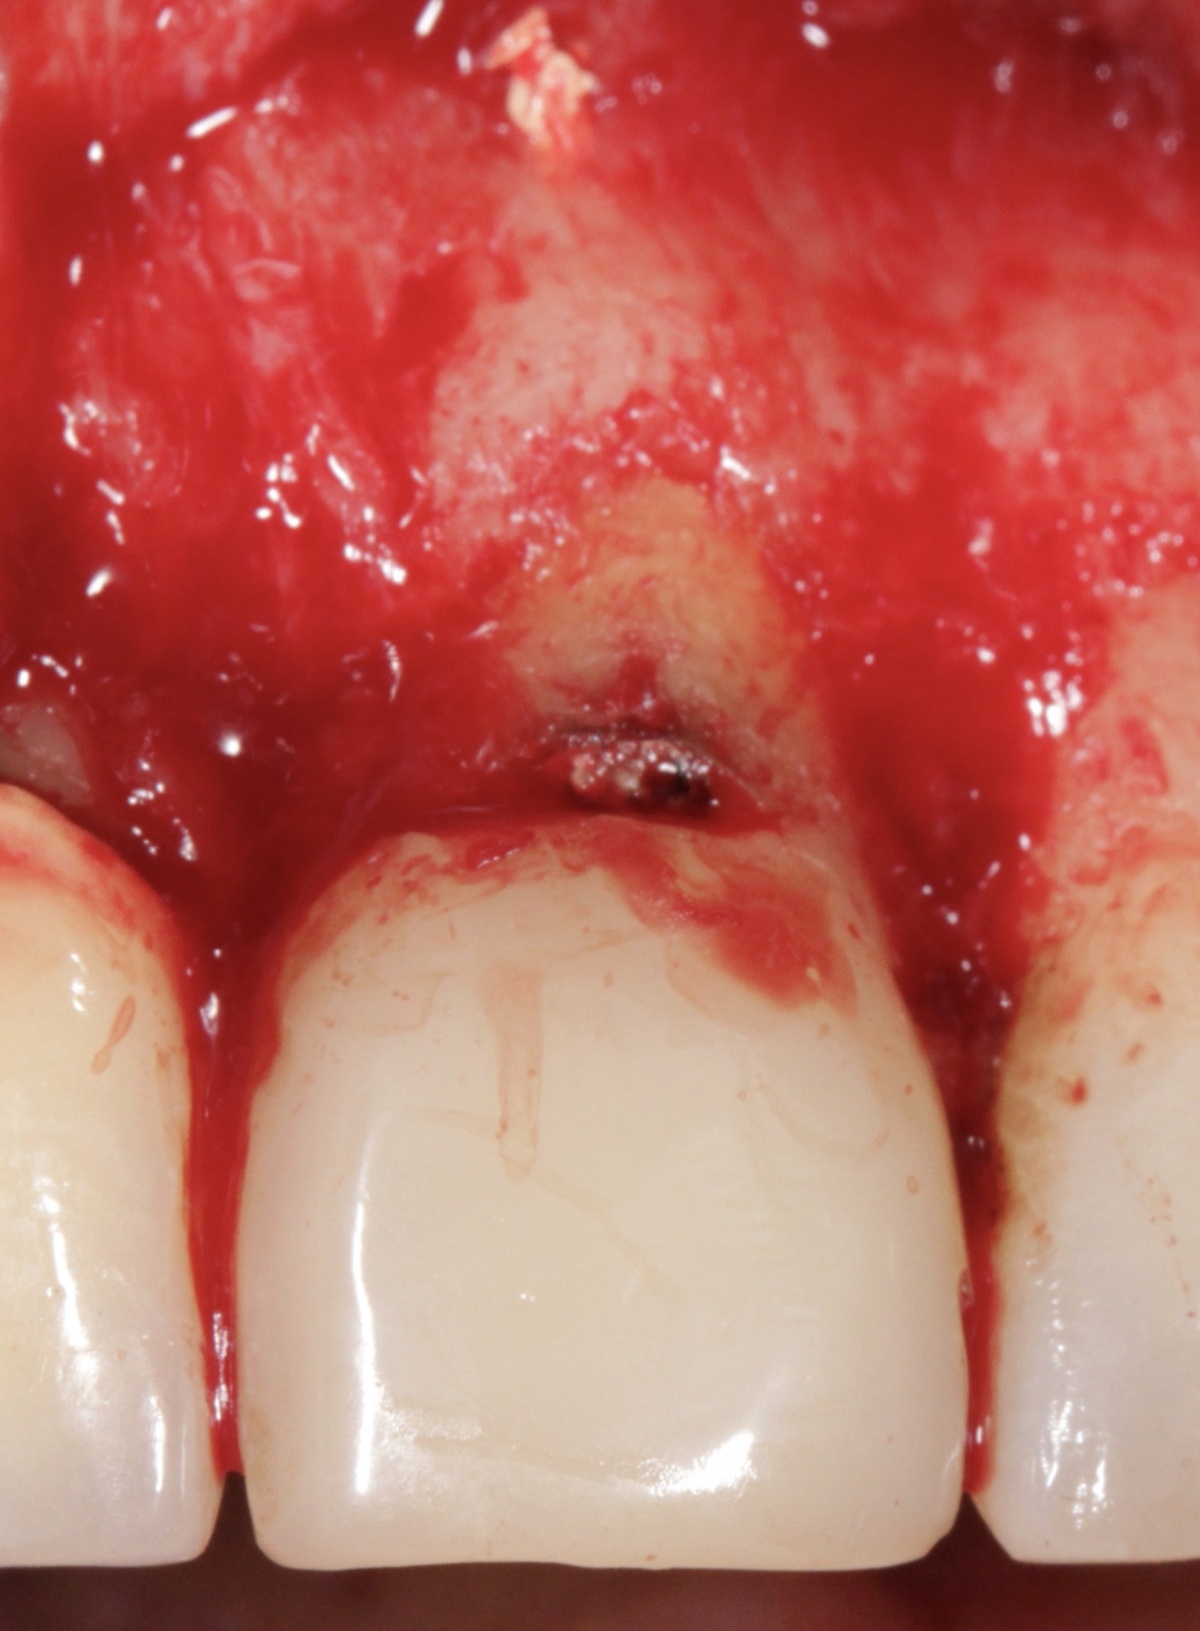

Ende 2016 stellte sich ein 32-jähriger männlicher Patient mit profunder Periimplantitis an den Zahnimplantaten 011 und 012 in der Abt. XXIII – Zahnmedizin vor. Die Implantate wurden bereits 2007 alio loco mit simultaner lokaler Knochenspreizung (Bonesplit) inseriert. Klinisch zeigten sich zwei Tissue-Level Implantate (Straumann® Standard Plus) mit deutlichen lokalen Infektzeichen und ausgeprägtem Verlust des periimplantären Alveolarknochens bei Sondierungstiefen von 8 mm (Abb. 1). Die Prognose der Implantate war infaust, weshalb die Indikation zur Explantation gestellt wurde.